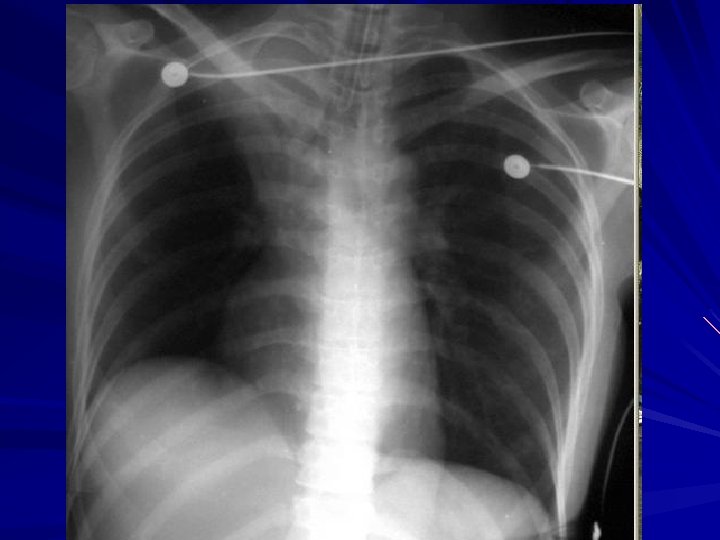

Pulmonary Edema Physical Examination: - Gallop Rhythm - ↑JVP - Basal Crackles - Lower Limb Edema Investigations: - CXR, ECG, ECHO Treatment : - Oxygen - Diuretics - Digoxin - After load Reduction

Pneumothorax v v Traumatic Spontaneous -Tall Thin

Pneumothorax Treatment: Chest Tube Insertion

Pneumonia History: - Cough - Shortness of Breath - Fever - Sputum Examination: - Dullness - ↑ Vocal fremitus - Bronchial Breathing - Crackles Treatment: - Oxygen - Antibiotics

Acute Respiratory Distress Syndrome Causes: - Aspiration Pneumonia - Near Drowning - Chest Trauma - Severe Pneumonia